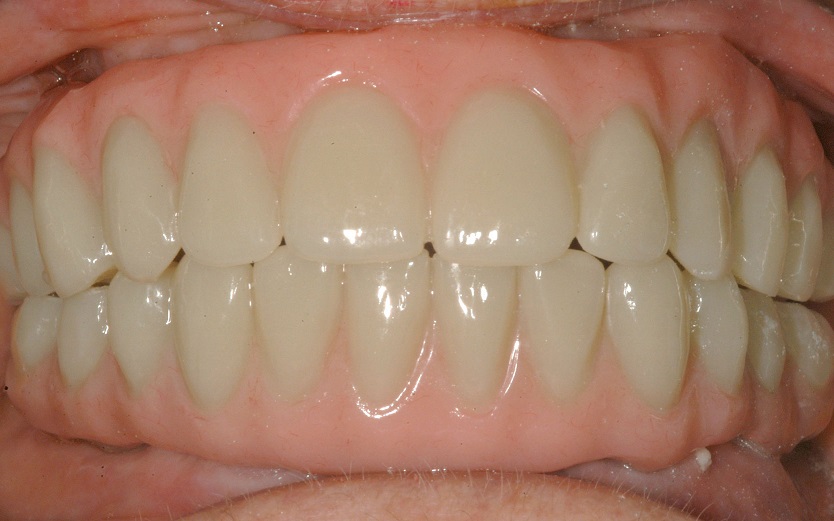

BEFORE + AFTER

After BarZero LTP Installation

Courtesy of Dr. Jon A. Ruel, DMD